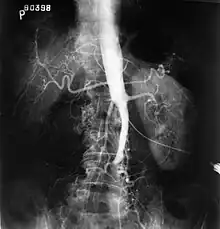

- Syndrome de Leriche : oblitération thrombotique de la bifurcation aortique[27].